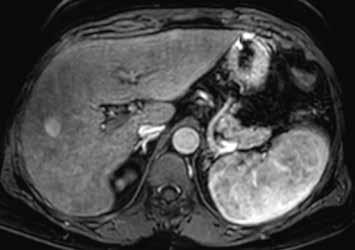

V centrální části ložiska je patrná vazivová jizva, která zůstává v arteriální fázi hypodenzní (9) a sytí se v pozdní fázi, kde je oproti zbytku ložiska hyperdenzní (13). Na MR je v T1-váženém obraze vazivová jizva hypointenzní (15), v T2-váženém obraze hyperintenzní (16).

Na MR ve fázi ekvilibria je v levém laloku patrné vcelku izointenzní ložisko s naznačeným hyperintenzním periferním prstenčitým lemem (17).